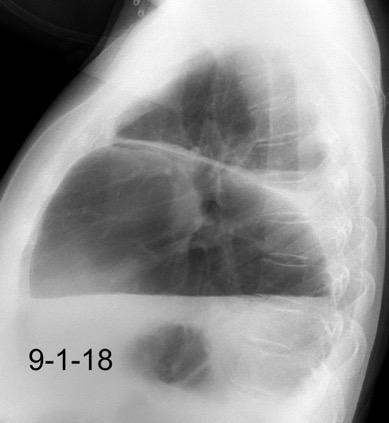

Paciente que ingresa con síntomas de colecistitis aguda. Antecedentes de trauma importante muchos años antes

Zhao L et al. Delayed traumatic diaphragmatic rupture: diagnosis and surgical treatment. © Journal of Thoracic Disease.

J Thorac Dis 2021

Asas

Líquido pericolecistítico

V. biliar con cálculos

Diafragma